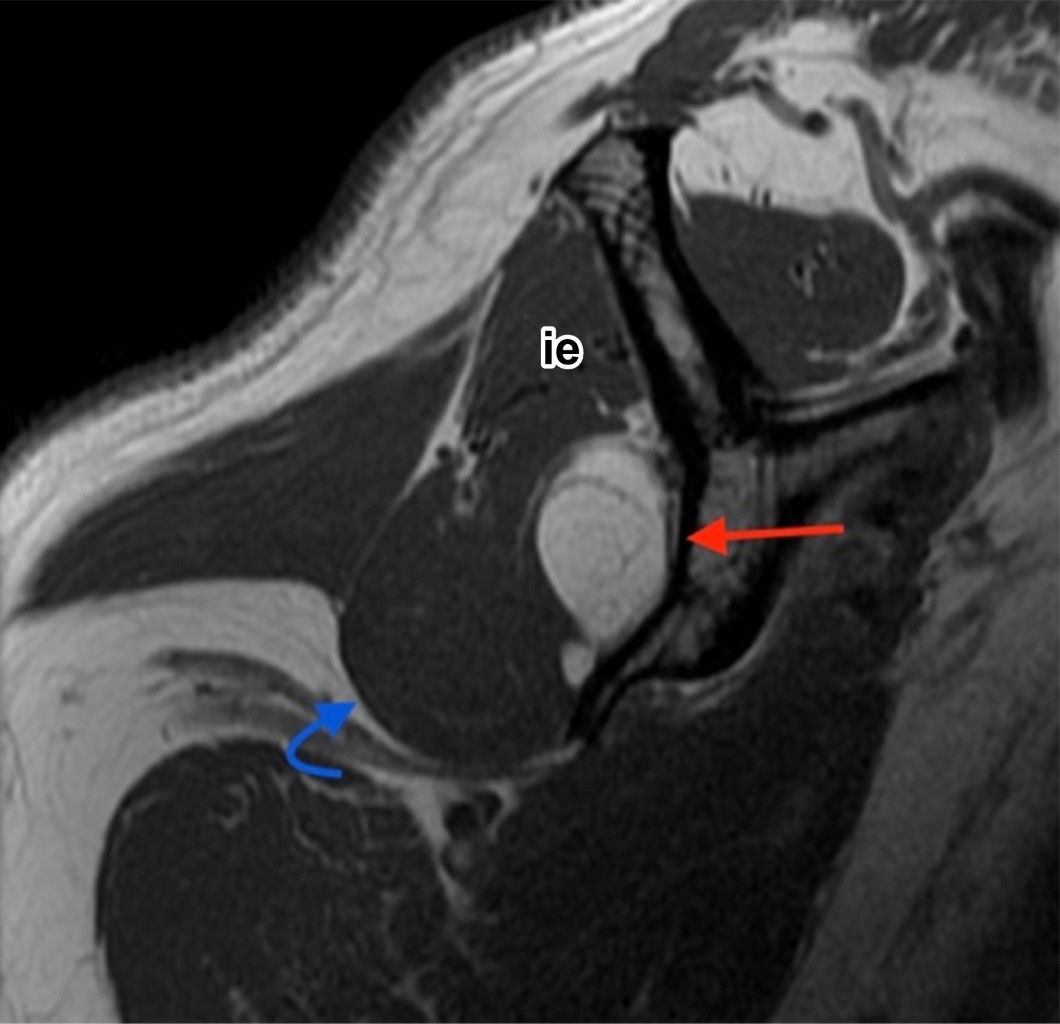

En el estudio de resonancia magnética entre fibras musculares del infraespinoso se observa imagen ovoidea, de márgenes bien delimitados, isointensa al tejido graso en secuencias T1, T2 y densidad protónica con saturación grasa, con diámetros aproximados en plano axial de 5.5 × 1.3 cm, en plano sagital de 3.1 × 1.4 cm y en coronal de 3.8 × 2.9 cm, con imágenes lineales internas hipointensas en todas las secuencias menores de 2 mm (Figura 1). La lesión se extiende por toda la fosa infraespinosa con involucro de algunas fibras musculares del redondo menor y desplaza levemente el infraespinoso (Figura 2).

La resonancia magnética es el estudio de imagen óptimo para valoración de lesiones lipomatosas de localización profunda.1 Se valora el tamaño y morfología, homogeneidad, márgenes, si es uni o multinodular, presencia o ausencia de estructuras lineales y su grosor (delgados < 2 mm, gruesos > 2 mm).5 Su morfología puede ser redonda, oval, fusiforme, irregular poligonal o en forma de pesa y usualmente no encapsulados.3 Caracterización tisular: tienen alta intensidad de señal en T1 y T2 y suprimen similar a la grasa en secuencias de supresión grasa. Los intramusculares contienen fibras musculares entremezcladas, isointensas al músculo normal en T1 y T2. Estas interdigitaciones muestran una apariencia estriada patognomónica de estos lipomas.3